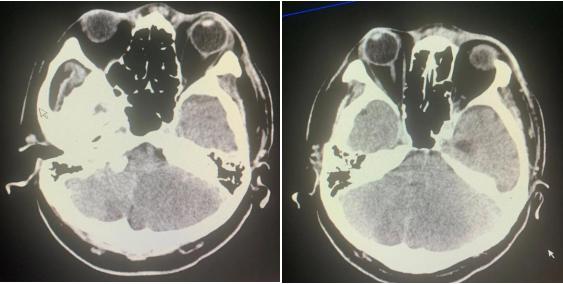

当做过头颅MRI检查后,老雷的疾病也明确了诊断——双侧小脑多发梗死,以左侧为重。

复查的头颅CT给了我们答案:小脑梗死及水肿加重,第四脑室梗阻,出现幕上梗阻性急性脑积水。